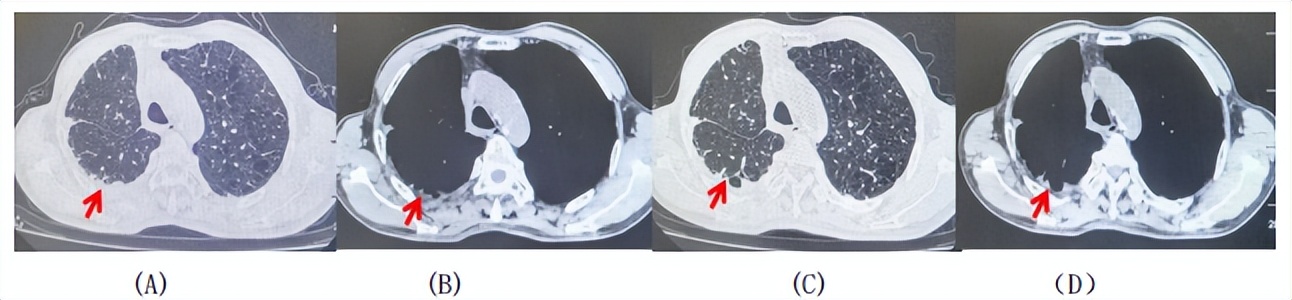

69岁男性,无糖尿病、高血压、心脏病等基础疾病,无吸烟、饮酒史,无肿瘤家族史。2023.06.07行胸部CT检查:右肺上叶胸膜下见肿物影,大小约33mm×22mm,边缘可见分叶,考虑恶性病变可能性大,双肺间质改变(如图1)。2023.06.14行“单孔胸腔镜下右肺上叶切除、肺门及纵隔淋巴结清扫、胸膜粘连松解术”;术后病理:(右肺上叶)腺癌(低分化,实体型占60%,不良腺体占40%),局灶伴神经内分泌标记表达(CD56、Syn),可见STAS及胸膜侵犯,未见确切神经侵犯及脉管内癌栓;(气管切缘)净;(淋巴结)未见转移癌0/26(2组0/2;4组0/6;7组0/2;对侧7组0/8;10组0/2;11组0/3;12组0/2;13组0/1)。术后分期pT2aN0M0 IB期,术后NGS基因检测:无驱动基因突变,PD-L1(22C3)TPS<1%。术后定期复查。

图1:患者手术前(2023.06)胸部CT肺窗及纵隔窗